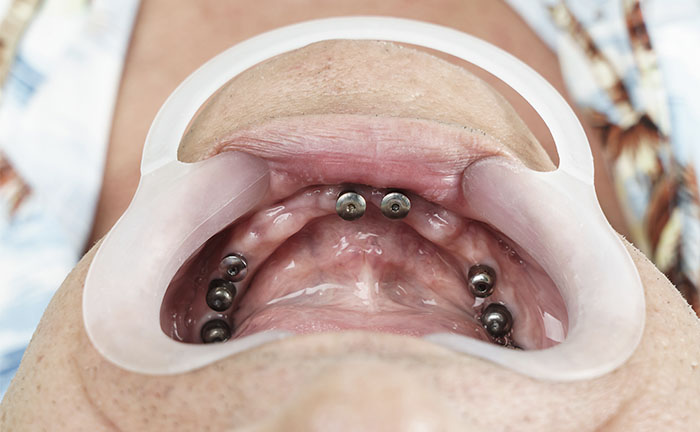

Implantology All on 6

The newAll on Six implant (All on 6) technique could be right for you if you already have a denture or a skeleton and you need to extract the last remaining teeth

• This operation is carried out after the panoramic and CT scan of the patient's dental arches;

• If there are certain conditions, the intervention can be performed with the transmucosal technique (at the discretion of the doctor).